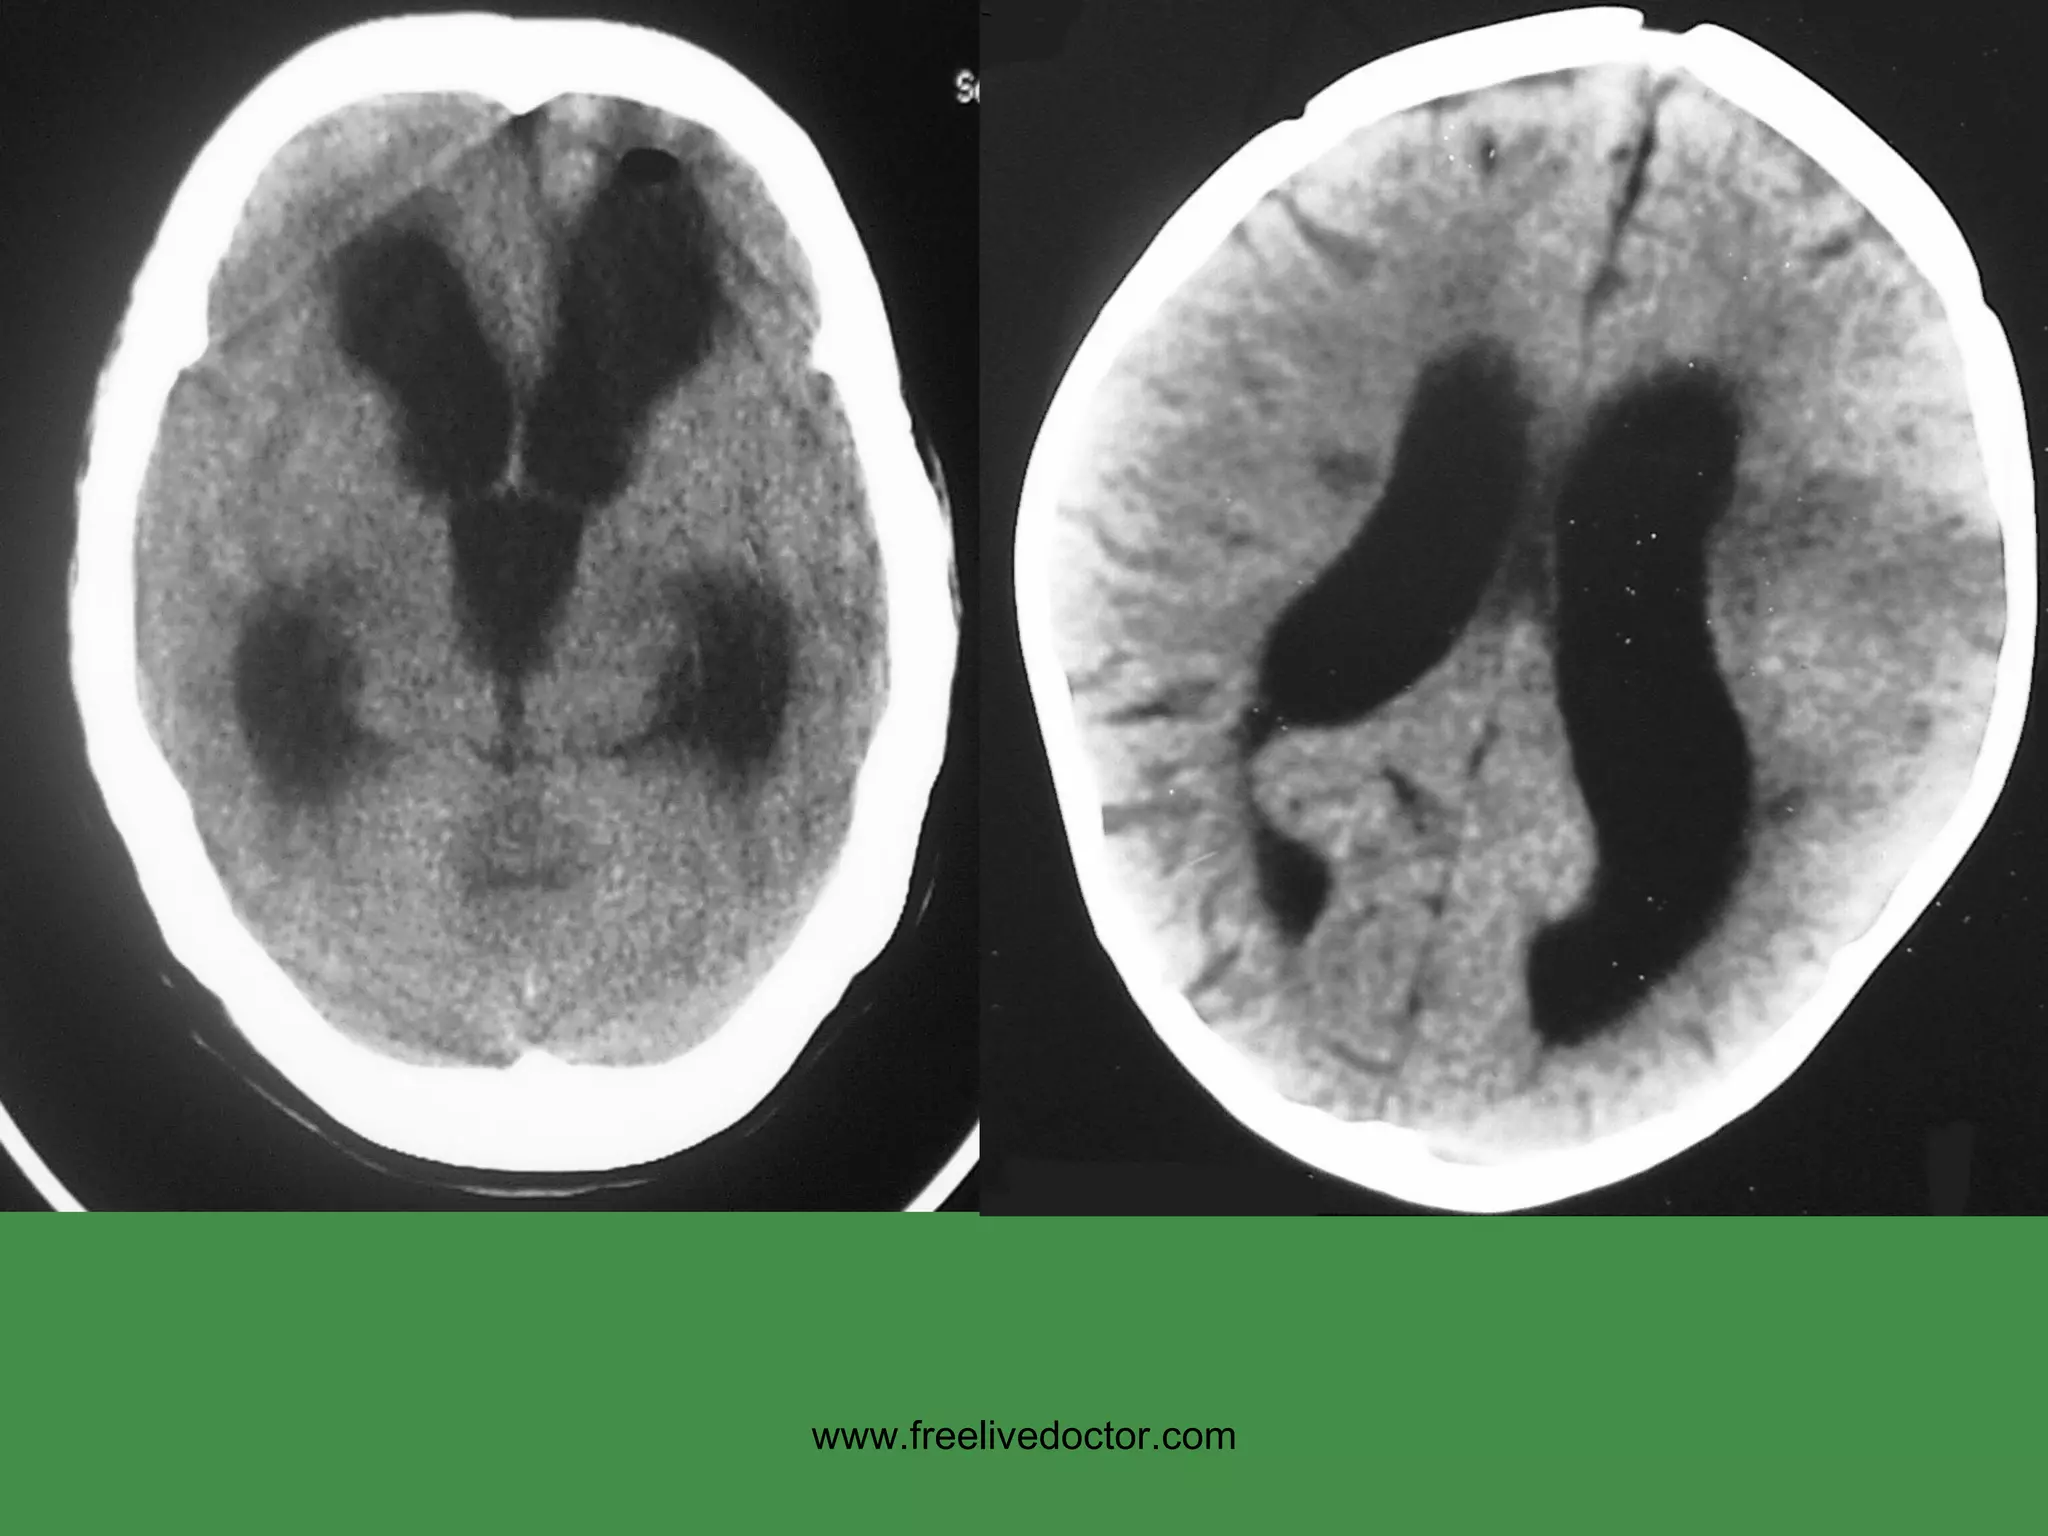

HYDROCEPHALUS www.freelivedoctor.com

HYDROCEPHALUS Impaired RESORPTION Increased PRODUCTION OBSTRUCTION COMMUNICATING (entire) NON-COMMUNICATING (part) HIGH Pressure NORMAL Pressure www.freelivedoctor.com

• #28 Basic pathophysiologic concepts about hydrocephalus which is defined as any major deviation from the normal physiology of CSF

• #29 Hydrocephalus on CT

• #30 Hydrocephalus on MRI

• #31 Hydrocephalus also showing cerebral edema, CT or MRI? Ans: CT Why? Ans: Bone is always very dense on CT, and water is always intense on T2 weighted MRI

• #32 Hydrocephalus, dilated ventricles